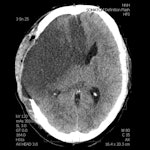

Different parameters are used in routine clinical practice for the detection of penumbra with CT and MRI. The subtraction of cerebral blood flow (CBF) and cerebral blood volume (CBV) is the usual way to detect penumbra using CT, according to the authors. On MRI, a subtraction between perfusion parameters (mean transit time, time to peak, or CBF) and diffusion-weighted imaging, rather than CBV, is used because CBV (especially on MRI) is not sensitive enough to detect small lesions. Such lesions are easily detected with DWI, according to the authors. DWI, on the other hand, may underestimate the final stroke volume and grows into CBV over the time.

"The penumbra concept is far from straightforward, however, as a number of different factors determine whether the tissue will become necrotic, such as the time-dependent nature of morphological changes discussed previously," the authors wrote. "The situation is even more complicated because exact quantification of perfusion values (CBF, CBV) is rarely used in routine clinical practice. Thus, relying only on CBF/CBV mismatch might disqualify some patients that would benefit from intervention."

Even in critically hypoperfused tissue, only a part of the predicted final infarct volume became necrotic after thrombolytic therapy, they noted. For these reasons, no quantitative parameters related to the penumbra should be taken for granted, and neuroimaging of the penumbra based on the presence of mismatch on CT or MRI may bring ambiguous results in relation to treatment outcome.